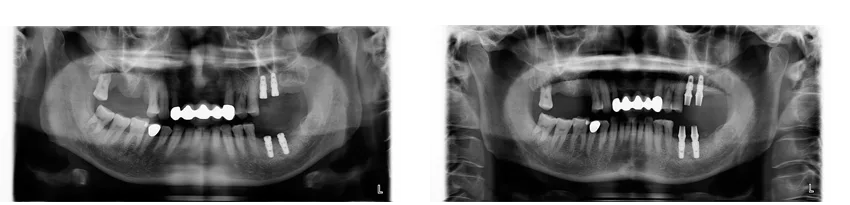

[ 王先生植牙案例 ]